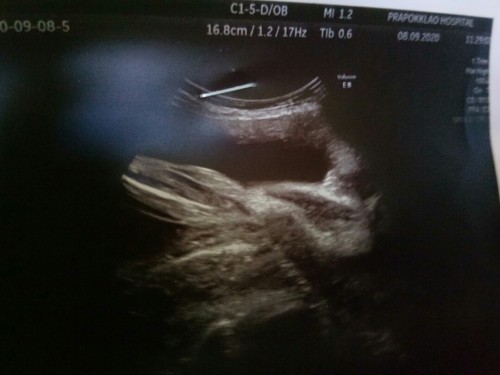

ได้ลูกชายจ้าา ทีมมกราคม 65

บ้านนี้ ลูกชายคนแรกค่าาา

แม่น้องเธียรเตอร์ครับ